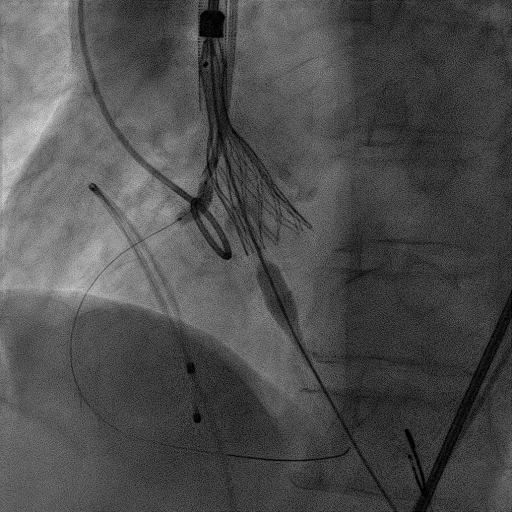

手术过程:

麻醉方式为全麻,建立静脉通路后,穿刺右侧股静脉,预埋ProGlide缝合器,食道超声指导下房间隔穿刺成功,鞘管扩张穿刺部位,沿导丝将导引导管送入左房,MitraClip调整后顺利到达二尖瓣目标位置,在X线及食道超声辅助下,将MitraClip NTR二尖瓣夹精确定位后,成功夹合二尖瓣A2-P2区,超声显示反流明显减少,多切面证实夹合组织充分,肺静脉多普勒波形由反向恢复正常,手术顺利结束,安返普通病房。

术中超声引导:

确定房间隔穿刺点:靠后

穿刺点高度测量:4.14cm

2D视图下测量大鞘长度2.2cm

2D视图下建立trajectory

3D视图打开夹子

3D视图下调Rotate,定位2区

X-plane:下夹子尝试捕获2区

夹子逐渐夹闭后,2区返流逐渐减少

3D:测量前叶长21.2mm,后叶长10.2mm

X-plane:计算前叶捕获长度6.8mm,后叶捕获长度6.5mm